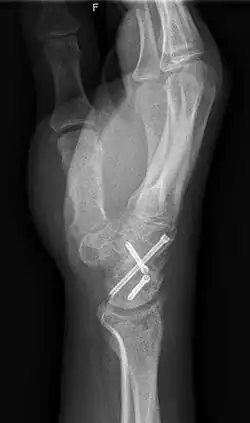

Arthrodesis

Arthrodesis is the surgical immobilization of bones within a joint to promote fusion of the joint.[20] Arthrodesis is performed most commonly on joints of the feet, hands, and spine.[21][22][23] Arthrodesis can relieve pain from arthritis and fractures.[24] This is accomplished through the use of orthobiologics such as allografts and autografts.[25] Allografts are done by creating bone grafts from a donor bone bank, whereas autografts are bone grafts from other bones in a patient's body.[25] Patient-reported outcomes following this procedure are typically positive in terms of long-term pain relief; however, the procedure also results in decreased range of motion.[26]